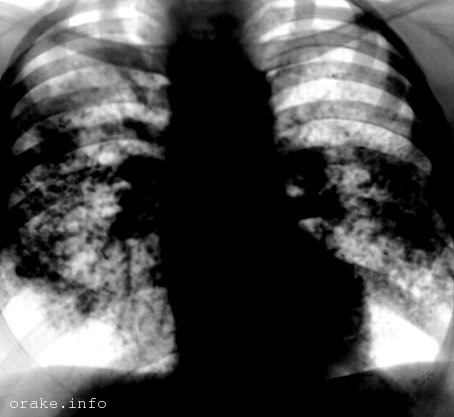

Что касается инструментального обследования, то в него входит рентгенография грудной клетки и томография, которые позволяют визуализировать увеличенные лимфоузлы в легких, фиброзные изменения и эмфизематозные участки.